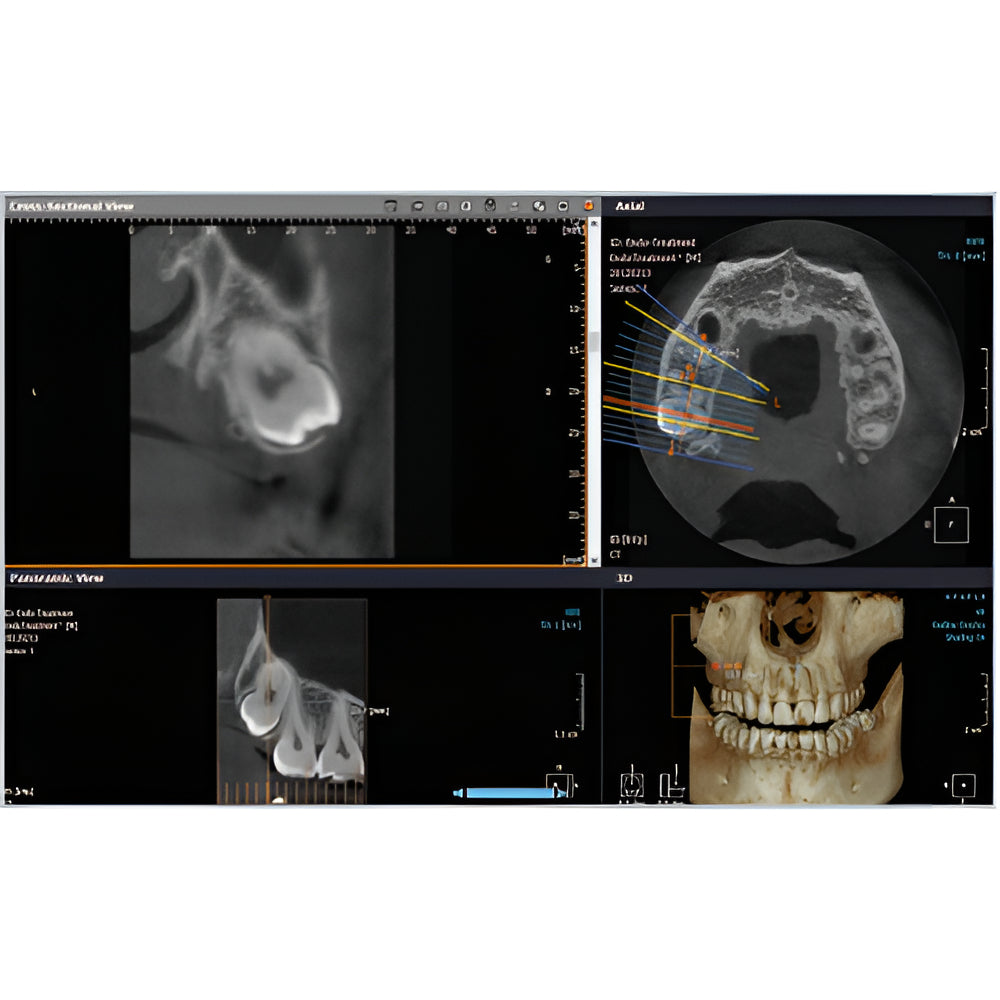

Rayscan Alpha brings another innovative technology with less Recon time and bigger FOV Size. And there are also new features – Fast scan mode, Object scan and Multi FOV.

- 2D/3D Imaging Software with License

- Multiple Scan Modes